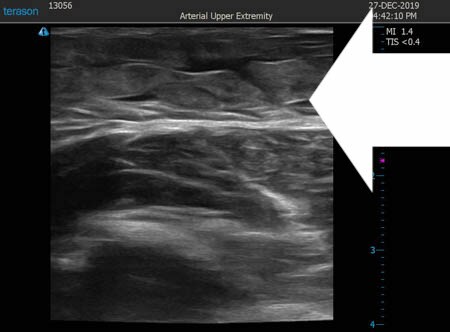

いつものように3Dタッチビュー(超音波)で

皮下脂肪層を評価してみましょう。

右二の腕

↓ ↓ ↓

上の画像の部分の皮下脂肪層をつまんでみましょう。